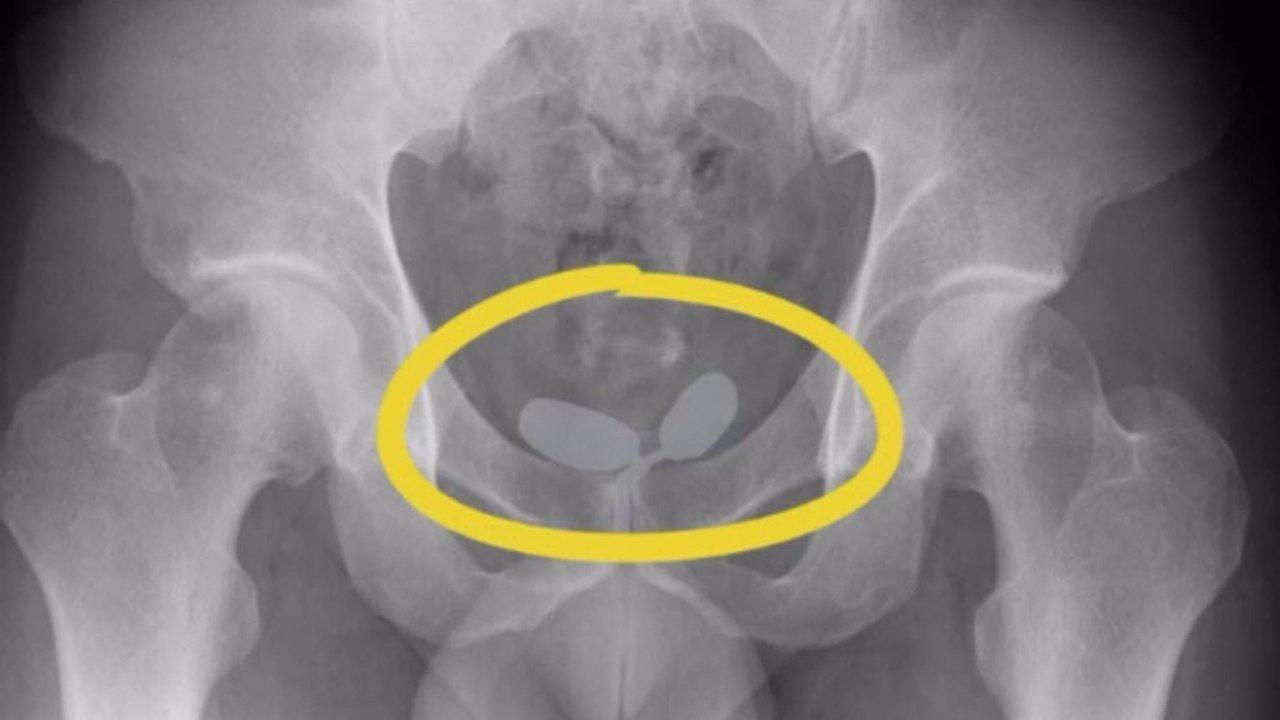

5 şüphelinin iç beden muayenesinde, prezervatifler içinde yutulmuş ve vücut boşluklarına gizlenmiş uyuşturucu olduğu ortaya çıktı.

İzmir'de, havalimanında kontrol edilen 2'si Alman uyruklu 5 şüphelinin iç beden muayenesinde, prezervatifler içinde yutulmuş ve vücut boşluklarına gizlenmiş, çeşitli tür ve miktarda uyuşturucu ele geçirildi. Şüpheliler gözaltına alındı.

Şüphelilerin yapılan iç beden muayenesinde, prezervatifler içinde yutulmuş ve vücut boşluklarına gizlenmiş halde 21,19 gram eroin, 12,70 gram kokain, 7,76 gram metamfetamin ve 7 sentetik hap ele geçirildi. Gözaltına alınan şüpheliler, polisteki işlemlerinin ardından bugün adliyeye sevk edildi.